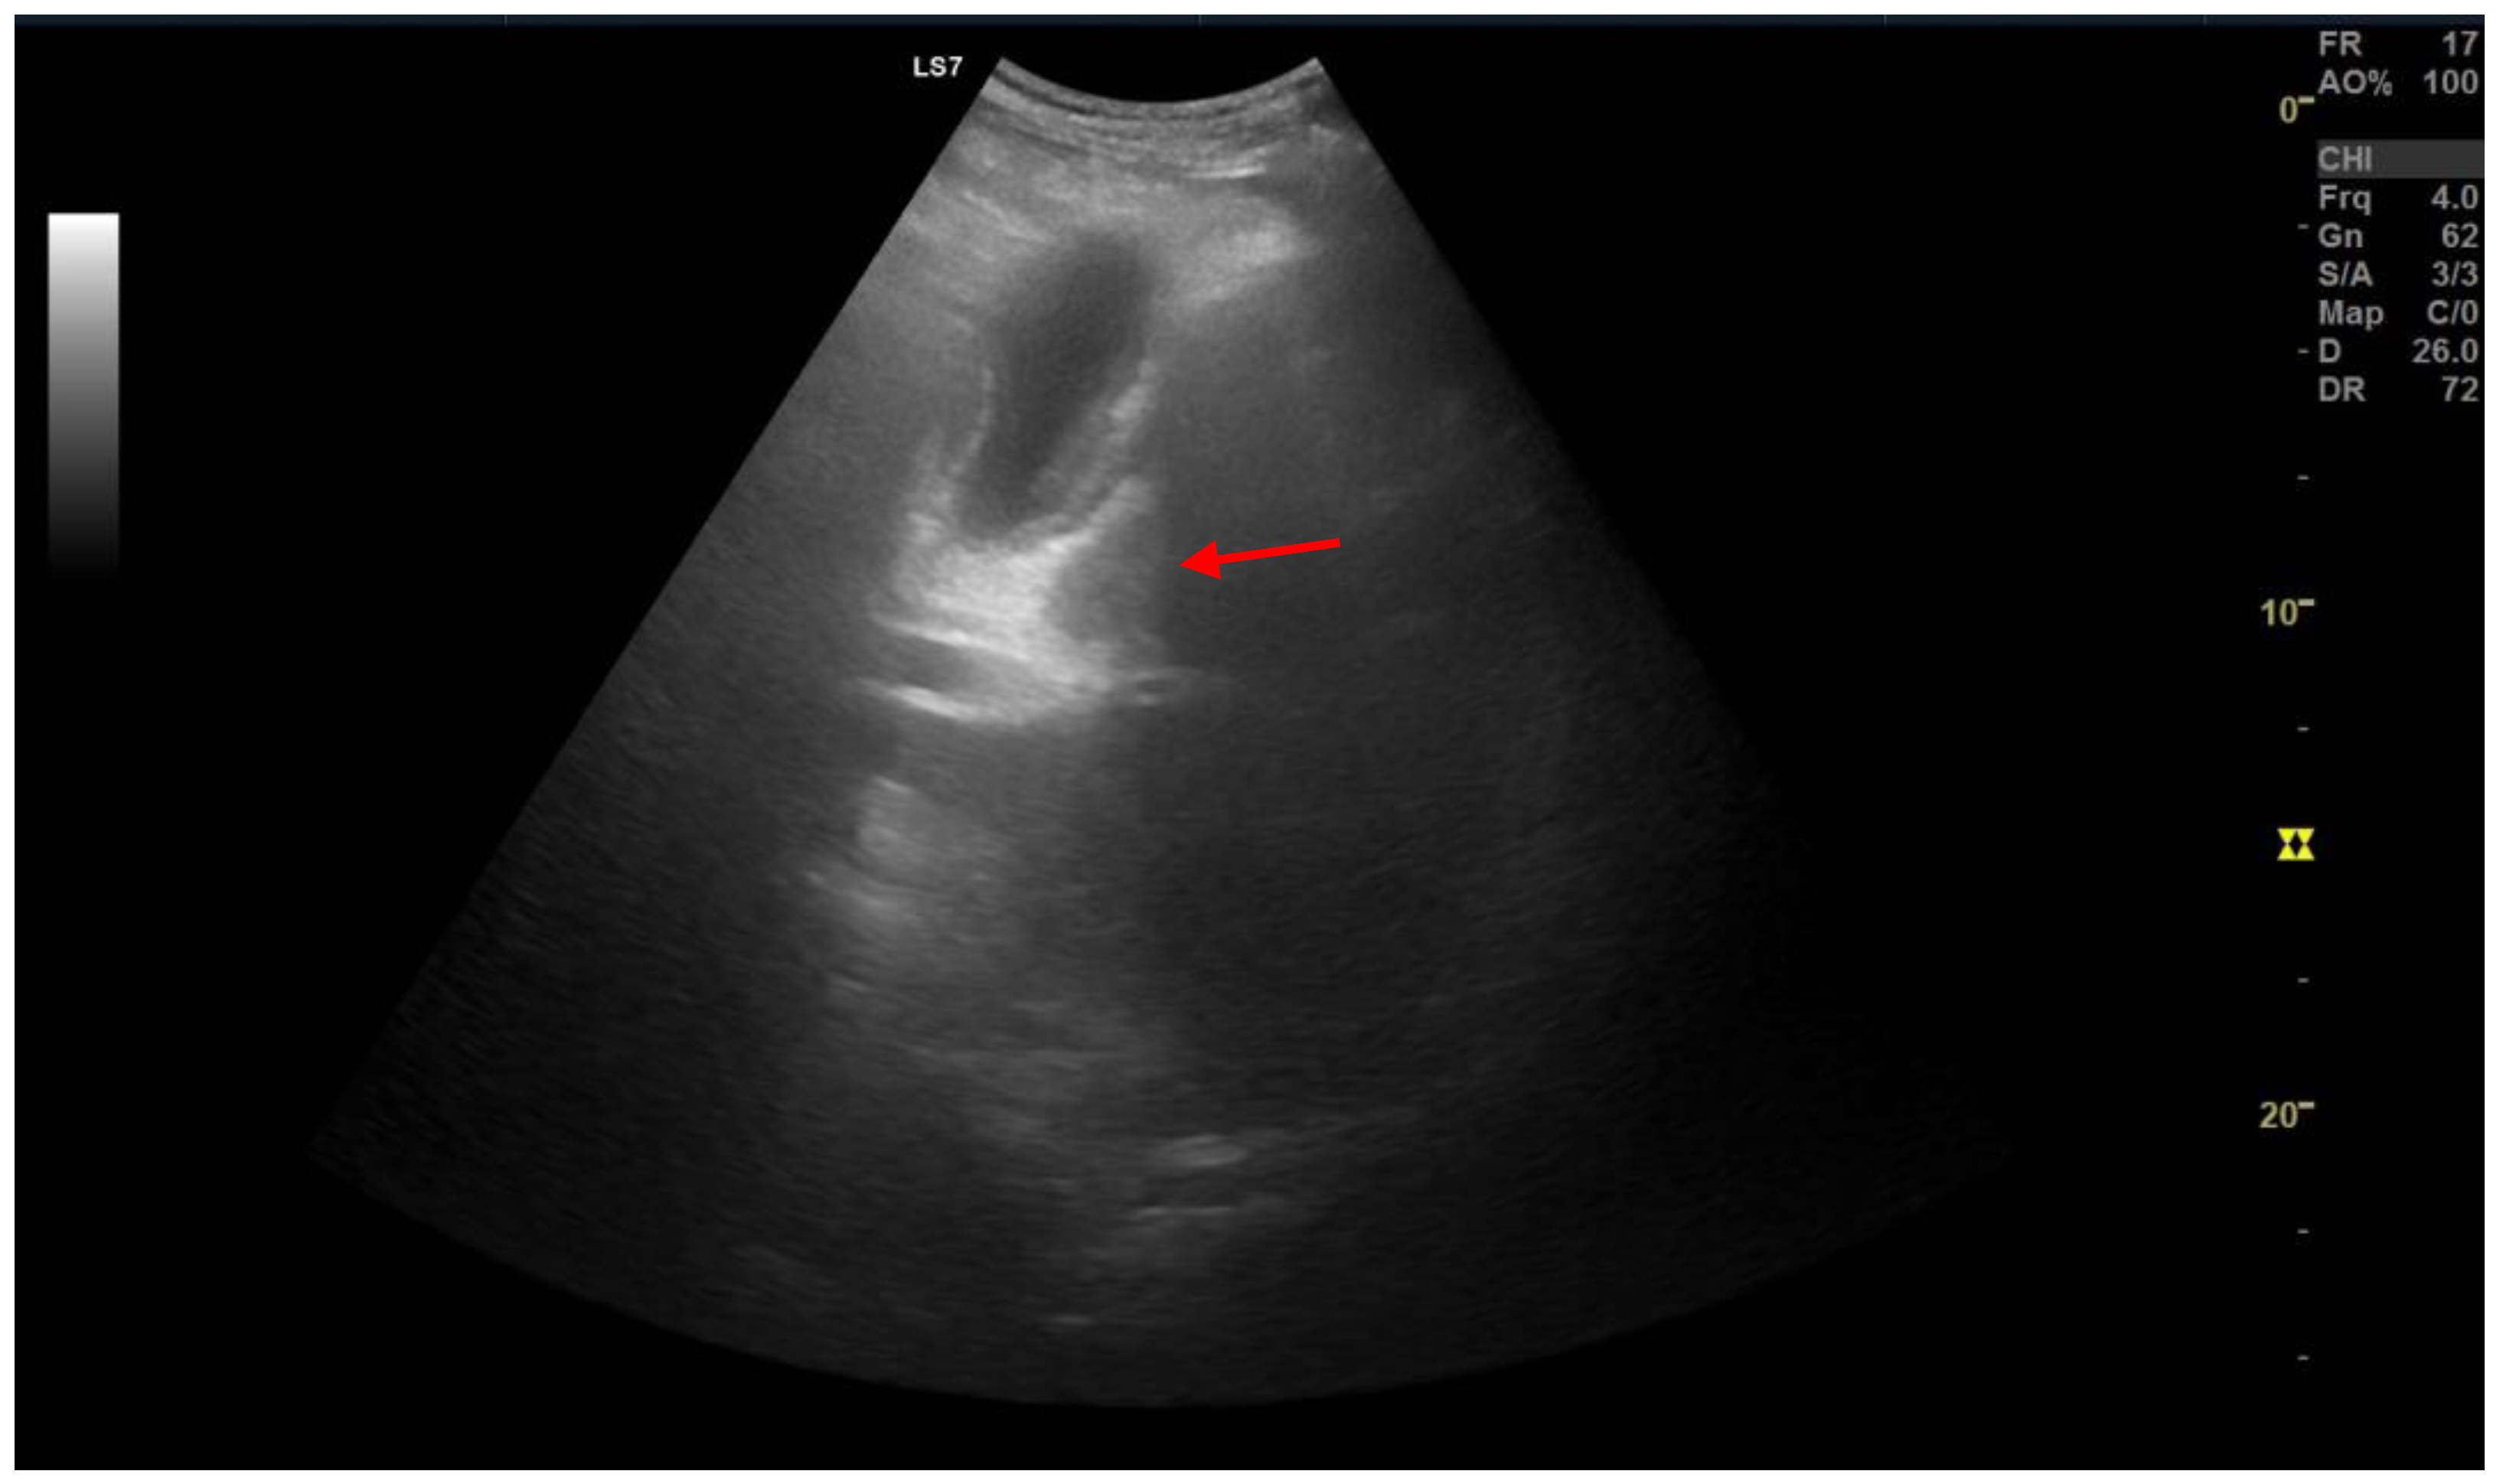

2. Types of Pancreatic Heterotopia

3. Discussion